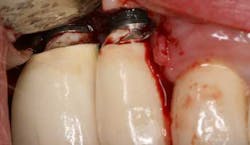

Fig. 7: Surgical intervention to remove retained cement.Author bioValerie Sternberg Smith, RDH, BS, has been a dental hygienist and surgical assistant in a practice limited to periodontics and implant surgery since 1984. She is on faculty in the Ashman Department of Periodontology and Implant Dentistry at New York University, College of Dentistry. She is a full member of the Academy of Osseointegration. She has sat on the editorial review board for the Journal of Practical Hygiene, and has been on the “Ask the Expert” Panel for Dimensions of Dental Hygiene. Valerie has lectured, published, and researched on the topic of preventive care for dental implants. References1. Wadhwani C et al. A descriptive study of the radiographic density of implant restorative cements. J Prosthet Dent. May 2010; 103(5):295-303. 2. Gapski R et al. Endosseous implant failure influenced by crown cementation: a clinical case report. Int J Oral Maxillofac Implants. 2008; 23:943-946.